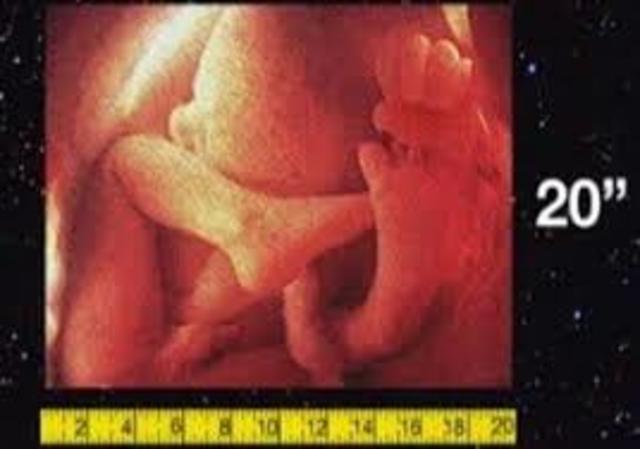

• semana 20 de embarazo

semana 20 de embarazo

Ya son 20 semanas de embarazo, ¡has llegado a la mitad del embarazo! Solemos hablar de 40 semanas de embarazo a partir de la última menstruación. Sin embargo, la duración puede variar de 37 a 42 semanas. En la semana 20 de embarazo el bebé mide aproximadamente 16 cm largo y pesa cerca de 255 gramos pero, como sabrás, al bebé le falta mucho por crecer.